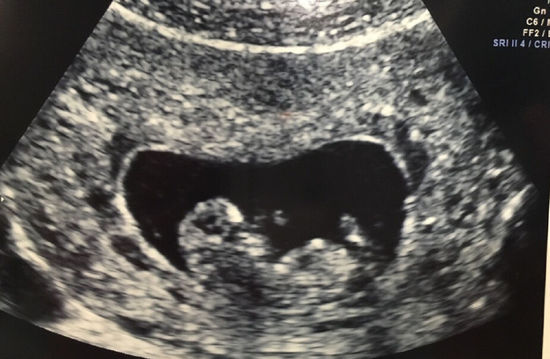

1、一般在停经35天至42天左右可进行B超检查,具体如下停经35天时此时B超检查可能观察到宫腔内出现圆形或椭圆形的妊娠囊这一阶段是早期妊娠的初步确认阶段,通过B超可直观看到孕囊位置,从而排除异位妊娠如输卵管妊娠的可能性但需注意,此时可能无法清晰观察到胚芽或原始心管搏动停经42天妊娠6;一般情况下,怀孕在6周左右B超可检查出来是否怀孕O;如果孕妇平时月经比较规律,一般怀孕40天左右,也就是停经40天做彩超,应该可以检查出孕囊的大小女性怀孕期间尤其是早孕,孕囊出现需要一段的时间,这是由于胚胎受精着床,并且能够在彩超下显现是需要一个过程的,正常受精卵移动到宫腔之内并且着床,需要大约12周的时间,也就是从同房的时间开始计算。

2、怀孕40天左右时,B超通常能够检查出来怀孕以下是关于怀孕多久B超能够检查出来的详细解答普通孕妇的情况在怀孕40天左右时,做B超通常能够看到明显的孕囊回声此时孕囊的直径大约在510mm左右,有时甚至能够看到孕囊内存在卵黄囊存在高危因素的女性对于既往有过宫外孕生化妊娠胚胎停育等高危因素的;怀孕对女人来说是非常幸福的事情,意味着一个小生命的到来当然有些人怀孕比较顺利,有些人怀孕会出现意外,比如宫外孕的出现,对女性就会造成比较大的伤害,所以要通过b超来及时检查那么,怀孕多久b超能查出来宫内宫外首先,一般在停经50天左右,就可以清楚的检查胎儿是在宫内还是宫外如果是正常的;停经35天时就可以去医院做B超检查来看出是否怀孕具体情况如下停经35天此时往往能看见宫腔内圆形或者是椭圆形的妊娠囊妊娠六周可以见到胎芽和原始心管搏动妊娠1113周+6天通过测量胎儿头臀长度,能够较准确地估计孕周,并校正预产期此外,妊娠早期的超声检查主要目的是确定宫内妊娠,排除异位;妊娠后大约5周B超能查出,怀孕40天左右B超能看出孕囊具体分析如下妊娠多少天B超能查出 通过B超检查中孕囊大小可以推算出大约受孕时间,但测量方面会有一定的误差,相差两三天是正常的怀孕多久B超能看出孕囊 孕囊定义孕囊是怀孕最初的形态,是原始的胎盘组织被羊膜血管网包裹的小胚胎 时间;回答问题分析 你好一般在怀孕后40天就可以通过做B超检查在宫腔内可以看到胎囊了,你可以一周后去医院做B超检查,B超对胎儿的辐射很小,可以放心的去做检查,你也可以去医院做血HCG检查是否正常,也可以 辅助诊断是否宫外孕,如果你怀孕后一切症状还好,也可以在孕50天左右是去医院做B超检查,那时就可以看到;怀孕多久可以做B超看出来,主要取决于孕妇自身的月经周期状况月经周期较短怀孕30多天时,经阴道超声可能看到小胎囊高龄孕妇通常月经周期较短,因此可能在这个时间点看到胎囊月经周期规律怀孕40多天时,做超声即可看出比较明显的胎囊经阴道超声比经腹部超声能早一周左右显示宫内胎囊孕67周左右;怀孕五到六周时,B超通常可以查出来具体分析如下对于月经规律的女性,可在停经五周后通过超声检查观察到子宫内出现小小的孕囊此时孕囊可能尚未完全发育,但已具备初步形态停经40天左右时,孕囊直径通常达到10毫米左右,此时通过B超可清晰确认宫内妊娠临床中可通过孕囊直径推算停经天数,公式为孕囊;怀孕后通常在停经6周左右可以做B超检查停经6周左右进行B超检查的原因在停经6周左右时,孕囊通常已经形成,此时通过B超检查可以较为清晰地观察到孕囊的位置这一检查能明确判断是宫内孕还是宫外孕,避免因宫外孕未及时处理而引发严重后果同时,还能检测到胎芽及原始心管搏动,从而初步评估胚胎的发育情况。

3、一般怀孕5周左右B超能看到孕囊在怀孕早期,受精卵着床后会逐渐发育形成孕囊通常情况下,停经5周左右时,通过经阴道超声检查,有可能发现宫腔内的孕囊这是由于经阴道超声检查相较于经腹部超声检查,具有更高的分辨率,能够更早地探测到宫腔内的微小结构然而,实际看到孕囊的时间并非绝对固定每个孕妇;怀孕后一般建议在6到8周进行B超检查以确认妊娠情况具体分析如下对于月经周期规律的女性,在末次月经后推5周即怀孕5周左右时,通过B超检查可能观察到宫内妊娠囊及胎心搏动此时若胚胎发育正常,可初步确认宫内妊娠但需注意,部分女性因排卵延迟或受孕时间较晚,胚胎着床时间可能推迟,导致妊娠囊。

4、怀孕最早在45周时通过B超能查出来具体说明如下最早时间通过阴道B超,最早在怀孕45周时可以发现非常小的像胎囊样的物质这里的45周是从末次月经的第1天开始算起典型胎囊出现时间通常在怀孕555周时,会出现典型的胎囊,此时卵黄囊也会出现,用B超可以基本上确定其是否为胎囊综合判断;因此,在进行B超检查以确认怀孕时,医生通常会结合孕妇的月经周期临床症状以及其他检查结果来做出综合判断如果孕妇对B超检查结果有疑问或担忧,建议及时咨询医生以获取专业的建议和指导总的来说,胚胎着床后通过B超检查多久能看出来怀孕是一个因人而异的问题一般来说,在怀孕5周左右可以通过阴道B超;怀孕后通常在停经56周可以通过B超检查观察到妊娠迹象具体时间受个体差异影响,需结合以下因素综合判断1 孕囊与胎芽的发育规律受精卵着床后,胚胎逐渐发育为孕囊停经5周左右,经阴道超声可能观察到宫腔内微小孕囊,但此时孕囊直径较小,结构尚不清晰至停经6周,多数孕妇可通过B超看到胎芽胚胎初步。